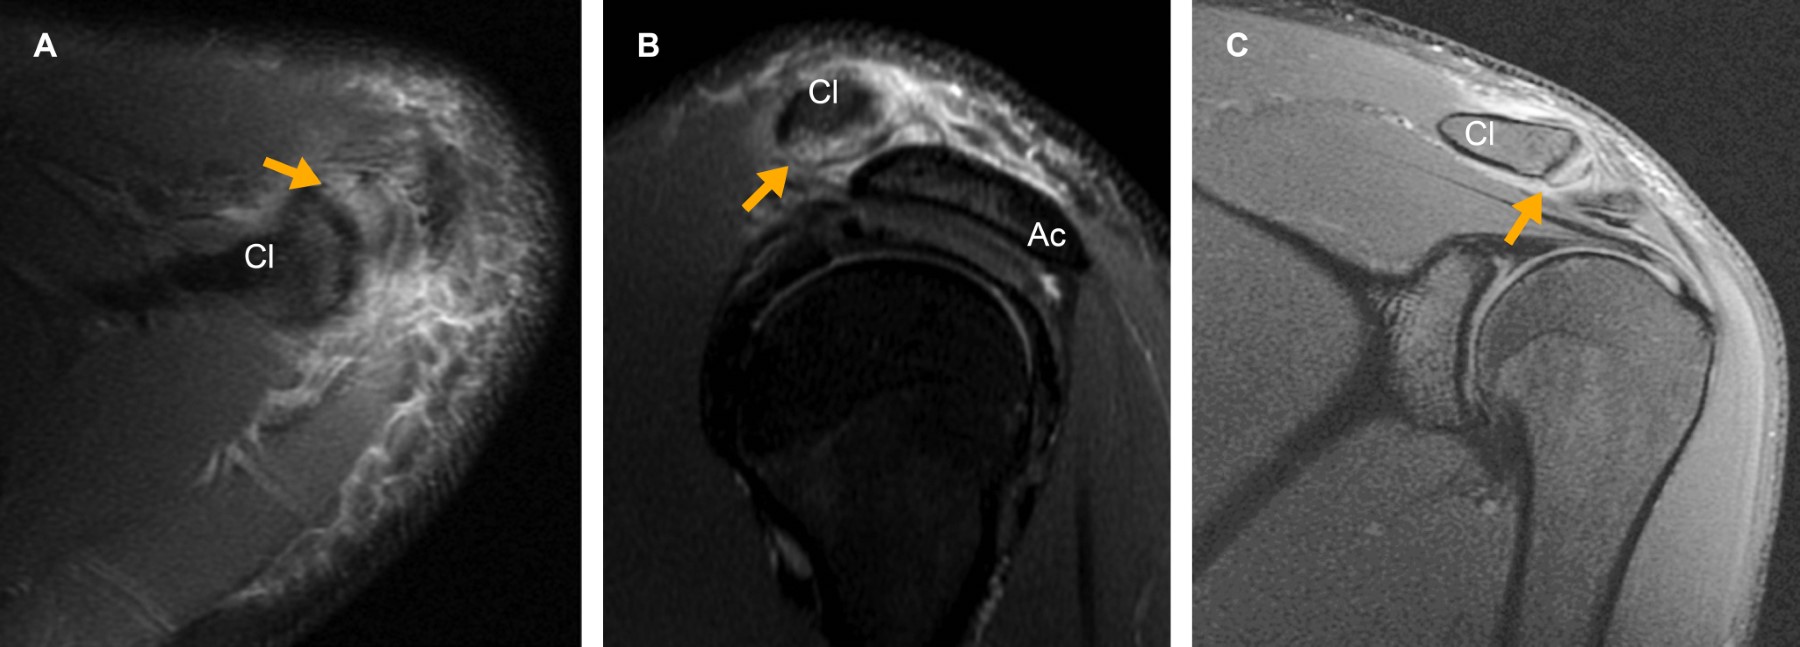

Osteolysis of the distal clavicle: underdiagnosed cause of shoulder pain

Introduction: osteolysis of the distal clavicle is an underdiagnosed cause of shoulder pain. There is no reported incidence in the literature. It is most frequently caused by repetitive microtrauma in patients who perform weightlifting or overhead sports. Case report: 22-year-old male with shoulder pain of one week of evolution. Conclusion: due to the increase in sports practice, osteolysis of the distal clavicle will be an increasingly seen entity, so it is essential to recognize the clinical picture and magnetic resonance findings, being the edema of the bone marrow the most frequent and characteristic.

Figure 2